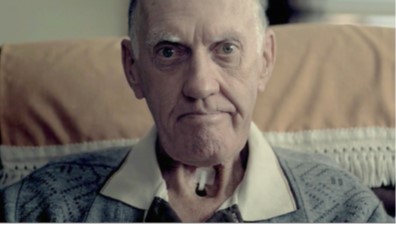

12. Smoking damages your gums and teeth

13. Smoking causes throat cancer